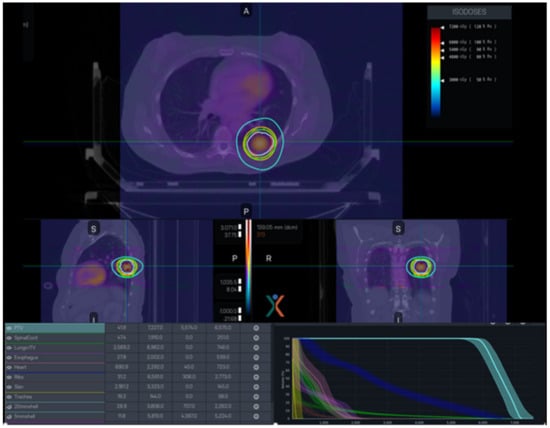

4.1. MRI-Based Online ART

- Henke, L.; Kashani, R.; Yang, D.; Zhao, T.; Green, O.; Olsen, L.; Rodriguez, V.; Wooten, H.O.; Li, H.H.; Hu, Y.; et al. Simulated Online Adaptive Magnetic Resonance–Guided Stereotactic Body Radiation Therapy for the Treatment of Oligometastatic Disease of the Abdomen and Central Thorax: Characterization of Potential Advantages. Int. J. Radiat. Oncol. Biol. Phys. 2016, 96, 1078–1086. [Google Scholar] [CrossRef]

- Keall, P.J.; Glide-Hurst, C.K.; Cao, M.; Lee, P.; Murray, B.; Raaymakers, B.W.; Tree, A.; van der Heide, U.A. ICRU REPORT 97: MRI-Guided Radiation Therapy Using MRI-Linear Accelerators. J. ICRU 2022, 22, 1–100. [Google Scholar] [CrossRef]

- Henke, L.E.; Olsen, J.R.; Contreras, J.A.; Curcuru, A.; DeWees, T.A.; Green, O.L.; Michalski, J.; Mutic, S.; Roach, M.C.; Bradley, J.D.; et al. Stereotactic MR-Guided Online Adaptive Radiation Therapy (SMART) for Ultracentral Thorax Malignancies: Results of a Phase 1 Trial. Adv. Radiat. Oncol. 2019, 4, 201–209. [Google Scholar] [CrossRef]